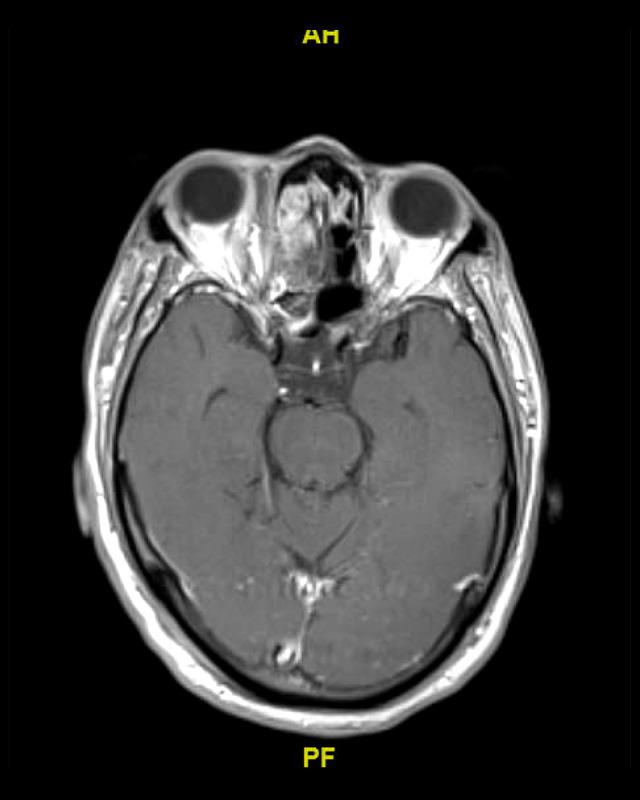

BACKGROUND We present a case of invasive sinusitis with rhinocerebral infection in a patient who had mild symptoms of COVID-19 infection and did not receive any immunosuppressive therapies. CASE REPORT A 49-year-old man with a history of uncontrolled diabetes presented to the hospital with multiple generalized tonic clonic seizures. He had recently been diagnosed with mild COVID-19 and was treated at home with supportive care only. He was found to have cerebritis in the right frontal lobe along with right fronto-ethmoid sinusitis. He underwent extensive testing with nasal endoscopy with gram stain and culture, cryptococcal studies, 1-3-Beta-D glucan, blood cultures, fungal CSF studies, Lyme disease, HIV, Fungitell assay, and galactomannan studies, which were all negative. He was started on i.v. antibacterial therapy with cefepime, vancomycin, and metronidazole along with amphotericin B. After 2 weeks, his repeat imaging revealed progression of cerebritis along with new early abscess. Given these findings, his antibiotics were changed to meropenem and the amphotericin B dose was increased. He was recommended debridement and sinus surgery but refused. During the course of treatment, he developed acute kidney injury and was switched to Posaconazole. Unfortunately, the patient decided to leave against medical advice 6 weeks into admission. He was advised to continue Posaconazole and levofloxacin but he could only afford levofloxacin. He was then recommended long-term levofloxacin. He has since recovered, with resolution of cerebritis noted in follow-up imaging 1 year later. CONCLUSIONS Our patient had mild COVID-19 infection and presented with secondary infective complications, which are usually associated with an immunocompromised state, despite receiving no immunosuppressives. It is imperative that all clinicians treating COVID-19 be watchful for fungal or bacterial co-infections in patients with active SARS-CoV-2 infection, even if the presenting symptoms are mild, particularly if other risk factors are present.

一名 49 岁男性,有未控制的糖尿病病史,因多发性全面强直阵挛发作到医院就诊。他最近被诊断为轻度 COVID-19,仅在家接受支持治疗。他被发现右额叶脑炎症伴有右额窦-筛窦炎。他接受了广泛的检查,包括鼻内镜革兰氏染色和培养、隐球菌研究、1-3-β-D 葡聚糖、血培养、真菌性 CSF 研究、莱姆病、HIV、Fungitell 检测和半乳甘露聚糖研究,结果均为阴性。他开始接受头孢吡肟、万古霉素和甲硝唑联合两性霉素 B 的静脉抗菌治疗。2 周后,他的重复影像学检查显示脑炎症进展,并出现新的早期脓肿。鉴于这些发现,他的抗生素改为美罗培南,并增加两性霉素 B 的剂量。他被建议行清创术和鼻窦手术,但被拒绝。在治疗过程中,他发生急性肾损伤,改为伏立康唑。不幸的是,患者在入院 6 周后决定出院。他被建议继续服用伏立康唑和左氧氟沙星,但他只能负担得起左氧氟沙星。然后建议他长期服用左氧氟沙星。1 年后的随访影像学检查显示脑炎症已消退,他已康复。